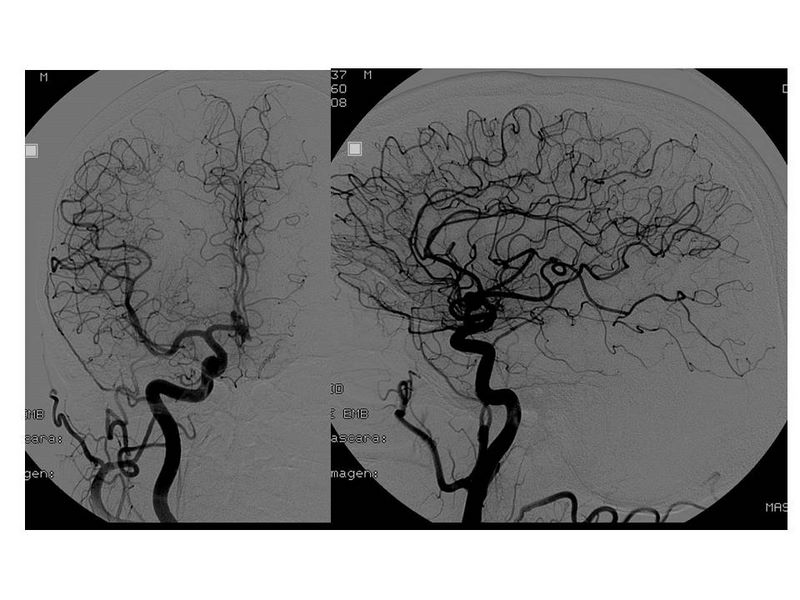

Aneurismas